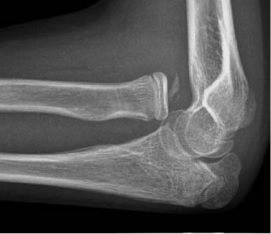

팔꿈치 질환 중 가장 흔한 유형은 부상이다. 팔꿈치 관절에는 세 개의 뼈가 있으며, 팔꿈치 골절은 이 뼈들의 어떤 조합과도 관련될 수 있다. 팔꿈치를 완전히 펼 수 있는 환자는 골절이 없을 가능성이 높으며(98% 확실성), 주두 골절이 배제된다면 엑스레이는 필요하지 않다.[27] 급성 골절은 엑스레이에서 쉽게 보이지 않을 수 있다.[28]

팔꿈치 탈구는 모든 팔꿈치 부상의 10~25%를 차지한다. 팔꿈치는 신체에서 가장 흔하게 탈구되는 관절 중 하나이며, 연간 급성 탈구 발생률은 10만 명당 평균 6건이다.[30] 팔꿈치 탈구는 어깨 탈구 다음으로 흔한 상지 부상이다. 팔꿈치 완전 탈구는 재정렬을 위해 전문적인 의료 처치가 필요하며, 회복에는 약 6주가 소요될 수 있다.

팔꿈치에서 가장 흔하게 나타나는 질병 유형은 부상이다.팔꿈치 관절에는 세 개의 뼈가 있으며, 팔꿈치 골절에는 이 뼈들의 어떤 조합이든 관련될 수 있다. 팔꿈치를 완전히 펼 수 있는 환자는 골절이 없을 가능성이 높으며(98% 확실성), 주두 골절이 배제된다면 엑스레이는 필요하지 않다.[27] 급성 골절은 엑스레이에서 쉽게 보이지 않을 수 있다.[28]

팔꿈치 탈구는 모든 팔꿈치 부상의 10%에서 25%를 차지한다. 팔꿈치는 신체에서 가장 흔하게 탈구되는 관절 중 하나이며, 연간 급성 탈구 발생률은 10만 명당 평균 6건이다.[30] 상지 부상 중에서 팔꿈치 탈구는 어깨 탈구 다음으로 흔하다. 팔꿈치의 완전 탈구는 재정렬을 위해 전문적인 의료 처치가 필요하며, 회복에는 약 6주가 소요될 수 있다.